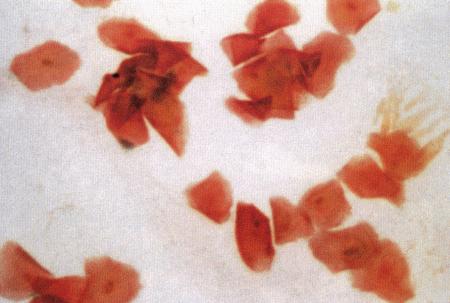

Вагинальная цитология

Повышение концентрации эстрадиола в период проэструса стимулирует деление клеток в базальных слоях вагинального эпителия, но затем концентрация эстрадиола, а соответственно и эндокринная поддержка образования нового, многослойного эпителия снижается, поэтому в образце обнаруживается больше мертвых ороговевших клеток. По мере развития проэструса снижается количество эпителиальных клеток, содержащих ядро. С начала до середины проэструса в вагинальных мазках обнаруживают повышенное содержание эритроцитов. Пик ороговения совпадает с началом повышения концентрации прогестерона; однако в начале эструса исследование не обнаруживает характерных особенностей, которые могли бы указывать на начало фертильного периода. Как правило, такой период наступает несколькими днями позже (табл. 1.1). Тем не менее вагинальная цитология остается популярным методом определения репродуктивного статуса суки из-за своей дешевизны, простоты и доступности. Для получения образца используют ватный тампон, предпочтительно небольшой, который вводят во влагалище и осторожно берут мазок. Полученные клетки помещают под микроскоп, а затем окрашивают контрастным (трихромом) или неконтрастным (например, препаратом Diff-Quik) веществом. При таком окрашивании мертвые кератинизированные клетки становятся оранжевыми, тогда как активные ядерные клетки, а также базальные и парабазальные эпителиальные клетки приобретают различные оттенки от голубого до зеленого.

Ближе к окончанию эструса вагинальные выделения претерпевают характерные изменения (снова выявляются эпителиальные клетки, содержащие ядро, и появляется большое количество лейкоцитов). Такая картина обычно наблюдается через 7–9 дней после пика ЛГ и известна как «вагинальный мазок метэструса». Изменению характера выделений предшествует переходный период, характеризующийся возрастающим количеством активных клеток и указывающий на окончание фертильного периода и эструса (табл. 1.1).

Вагинальная цитология весьма информативна в плане определения фазы эстрального цикла, однако значительные расхождения во времени появления основных признаков эструса по отношению к пику фертильности ограничивает применение указанной методики.

Фиг. 2.2.

Вагинальные выделения кошки (а). Выделения, типичные для фазы эструса. Большая часть клеток представляет собой безъядерные кератинизированные клетки или клетки с пикнотическим ядром. Присутствуют промежуточные клетки (b). Выделения, характерные для метэструса, — «течки», иногда наблюдаемой у кошек в конце эструса. Присутствуют поверхностные и промежуточные клетки, повышено содержание лейкоцитов. Этот короткий метэструс наблюдается в течение 24–48 часов (см. Приложение)